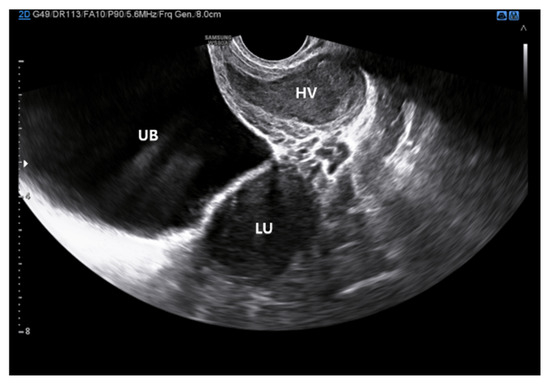

Mayer–Rokitansky–Küster–Hauser (MRKH) syndrome encompasses a range of Müllerian duct anomalies characterized by congenital absence of the uterus and the upper two-thirds of the vagina in young women who otherwise exhibit normal endocrine function and a 46,XX karyotype. MRKH syndrome can occur in an isolated form (type I) or in association with other congenital anomalies (type II or MURCS association), which may include renal, vertebral, auditory, and cardiac defects. It represents one of the most frequent causes of primary amenorrhea, affecting approximately 1 in every 4000–5000 women. MRKH syndrome often remains undiagnosed until a patient presents with primary amenorrhea, despite normal development of secondary sexual characteristics. Both genetic and non-genetic factors have been proposed as contributing to abnormal embryonic development, although the exact etiopathogenesis remains unclear. Imaging plays a key role in the evaluation of genital tract anomalies, allowing non-invasive and comprehensive assessment. Alongside physical examination and pelvic ultrasound, pelvic MRI is essential for identifying the presence of rudimentary uterine tissue. MRKH syndrome can have profound and lasting psychological impacts, making it essential for patients and their families to receive counseling both before and throughout treatment. A range of therapeutic options—both surgical and non-surgical—have been proposed for managing MRKH syndrome. Vaginal dilation remains the first-line treatment, as it offers high success rates with minimal risk of complications. Vaginoplasty is considered a second-line option for patients who do not respond to dilation therapy. Additionally, uterine transplantation and gestational surrogacy provide opportunities for women with MRKH syndrome to achieve biological motherhood. This review provides an updated overview of Mayer–Rokitansky–Küster–Hauser (MRKH) syndrome, encompassing its etiological, clinical, diagnostic, psychological, therapeutic, and reproductive aspects. We also present a case involving a 19-year-old woman with MRKH syndrome who presented with primary amenorrhea, highlighting the crucial role and advantages of MRI in diagnosis, differential assessment, and treatment planning. Full article

Figure 1